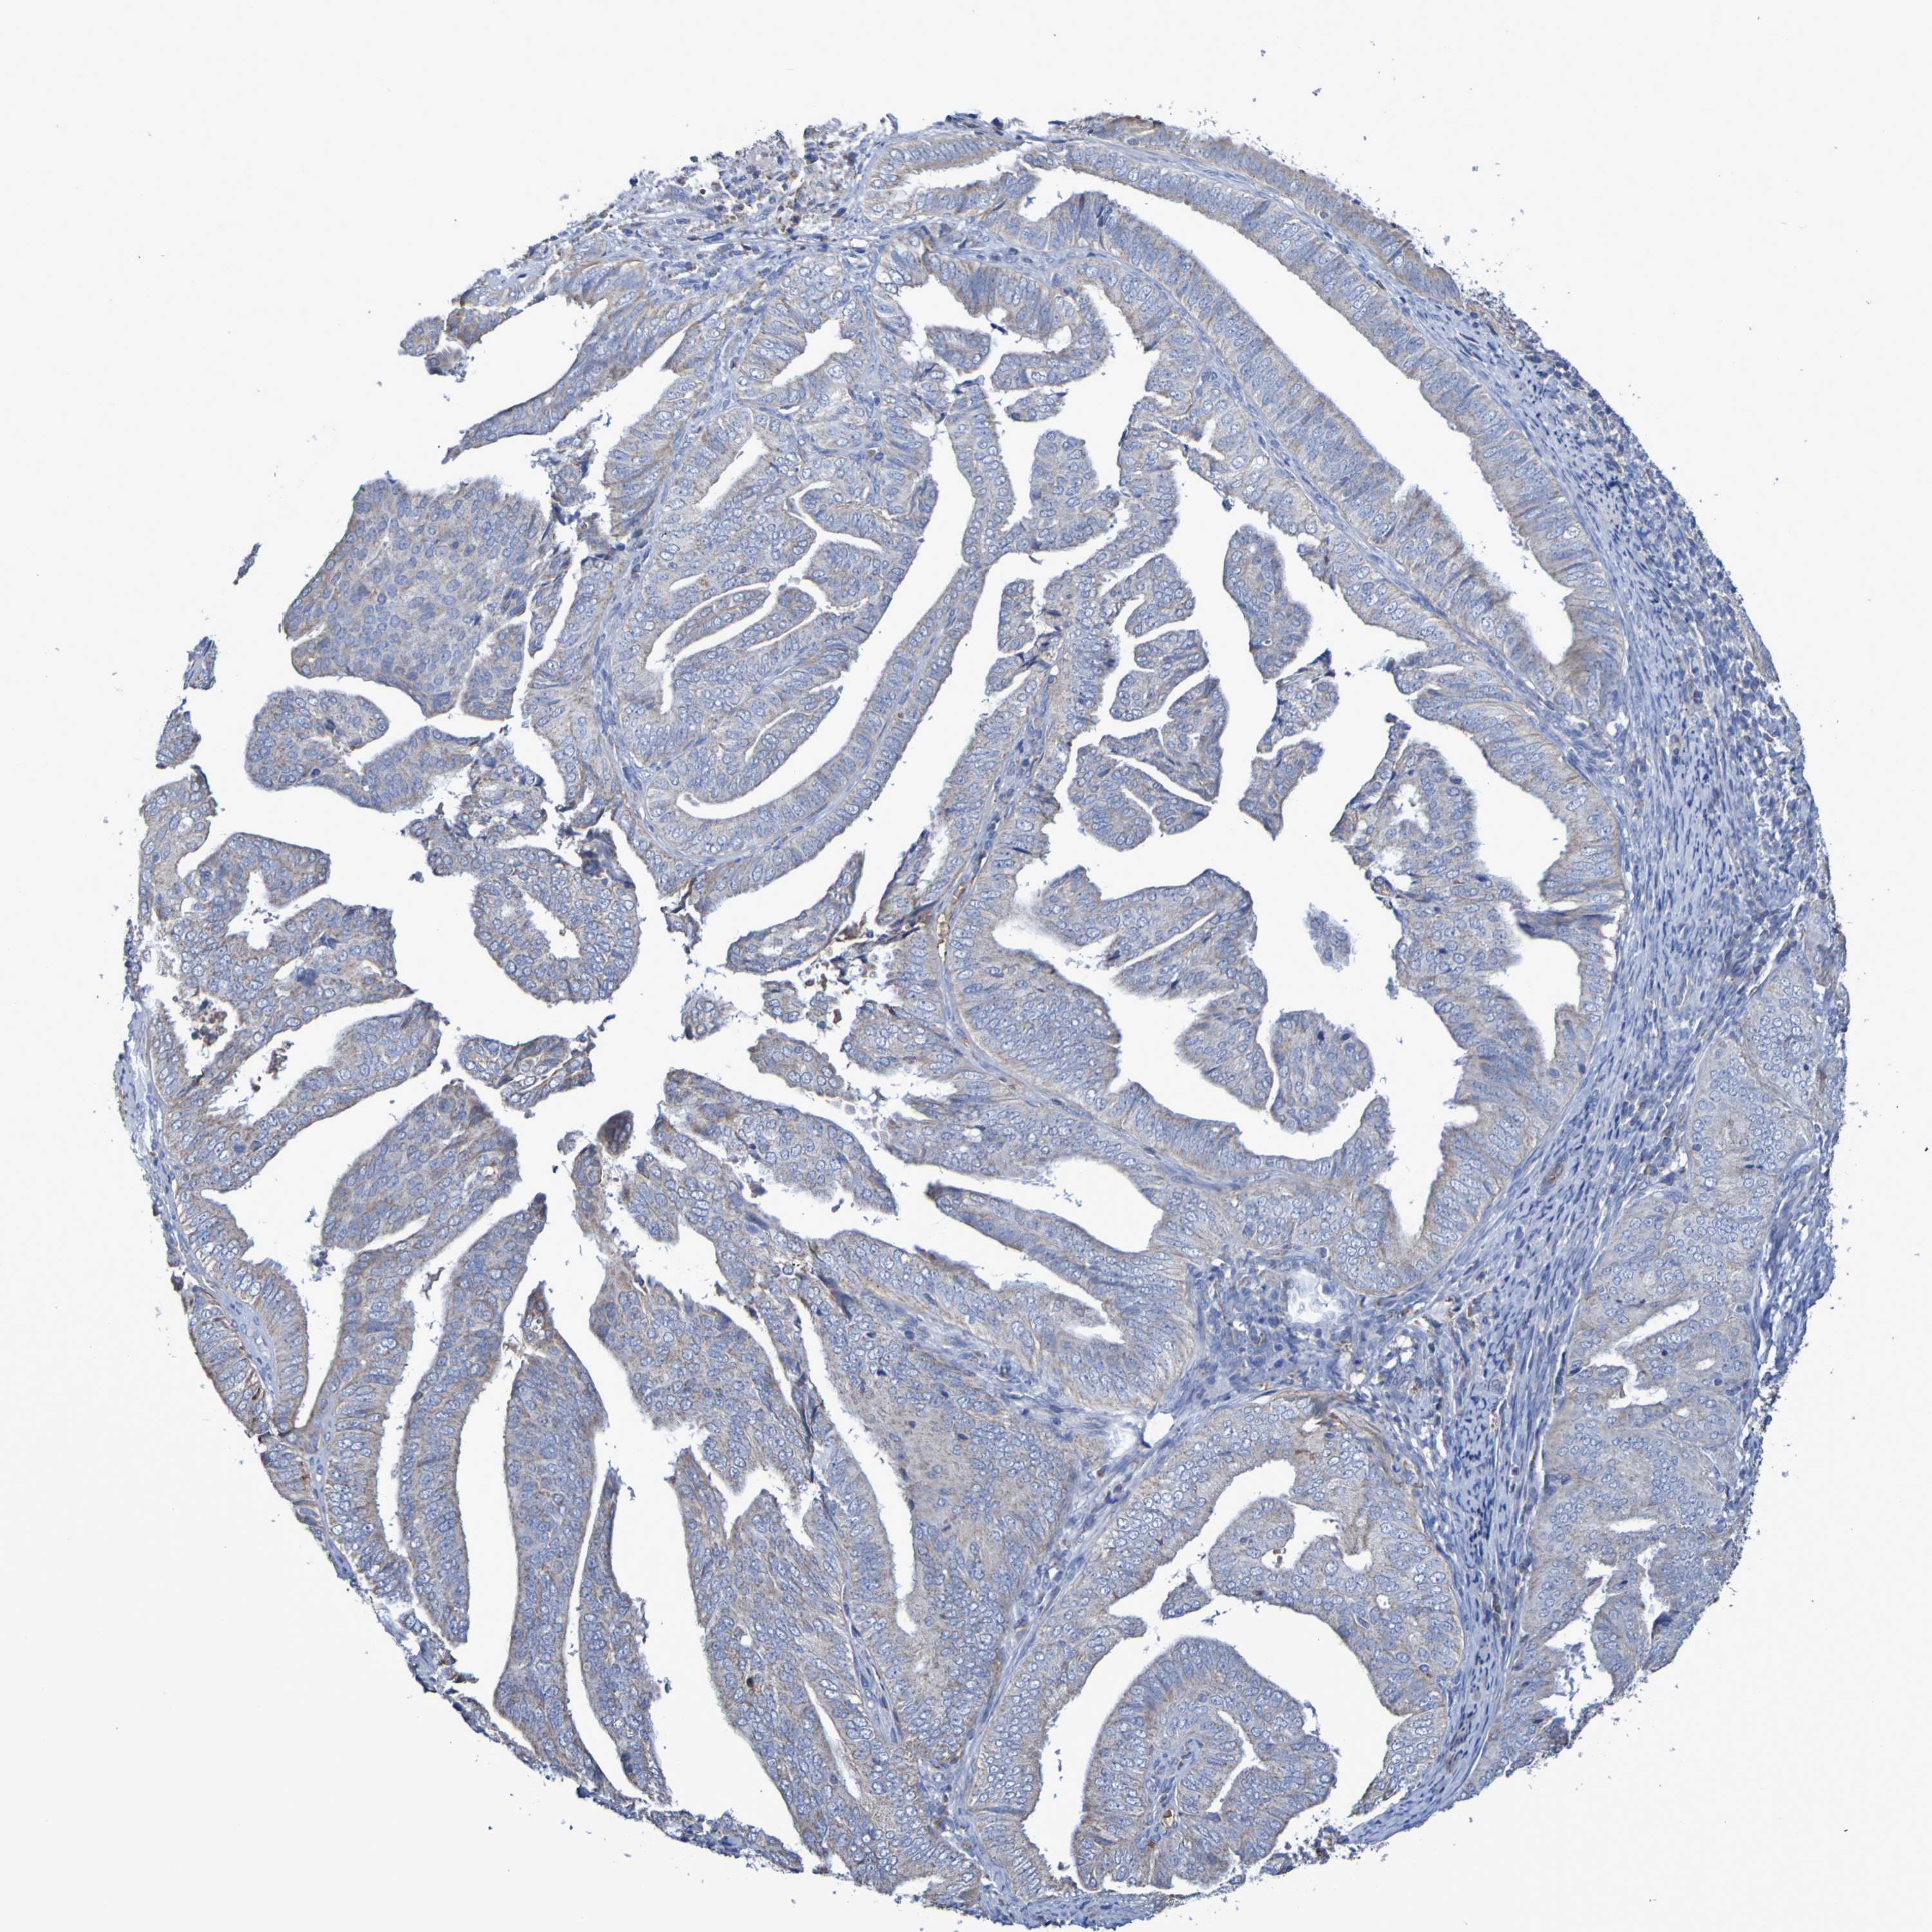

ENDOMETRIAL CANCER - Protein expressioni

A mouse-over function shows sample information and annotation data. Click on an image to view it in a full screen mode. Samples can be filtered based on level of antibody staining by selecting one or several of the following categories: high, medium, low and not detected. The assay and annotation is described here.

Note that samples used for immunohistochemistry by the Human Protein Atlas do not correspond to samples in the TCGA dataset.

Antibody stainingi

Antibody staining in the annotated cell types in the current human tissue is reported as not detected, low, medium, or high, based on conventional immunohistochemistry profiling in selected tissues. This score is based on the combination of the staining intensity and fraction of stained cells.

Each image is clickable and will lead to virtual microscopy that enables deeper exploration of all samples and also displays staining intensity scores, fraction scores and subcellular localization as well as patient and tissue information for each sample.

Antibody HPA001397

Antibody HPA012497

Staining

High

Medium

Low

Not detected

Intensity

Strong

Moderate

Weak

Negative

Quantity

>75%

75%-25%

<25%

None

Location

Nuclear

Cytoplasmic/membranous

Cytoplasmic/membranous,nuclear

Adenocarcinoma, NOS